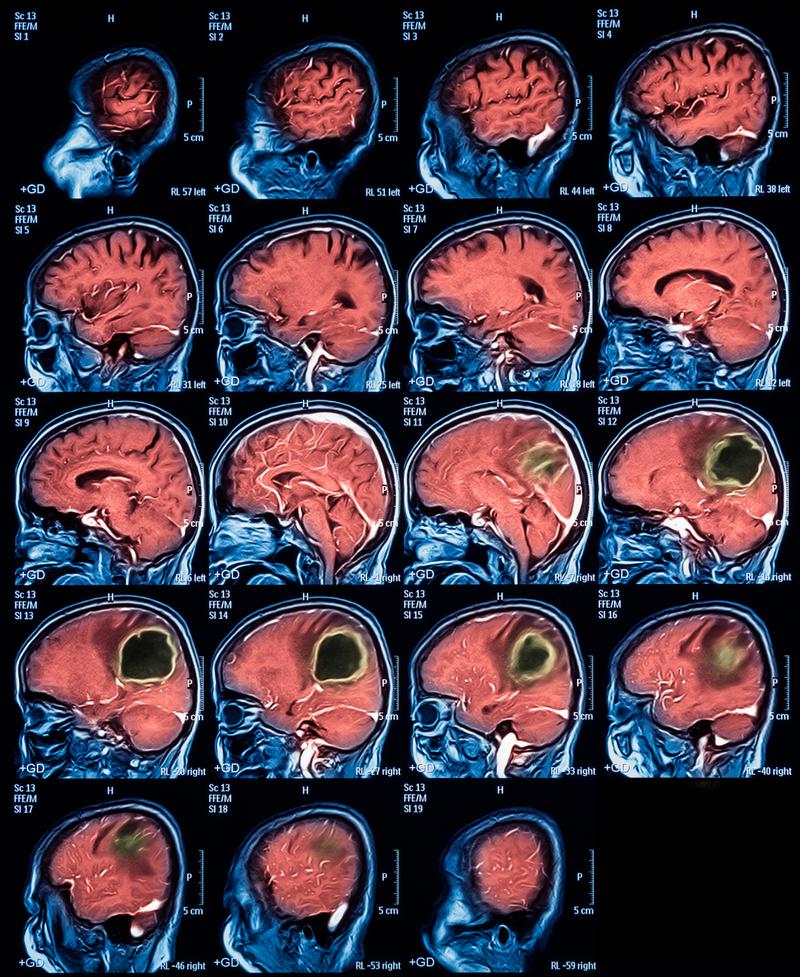

(图片来源网络,侵删)